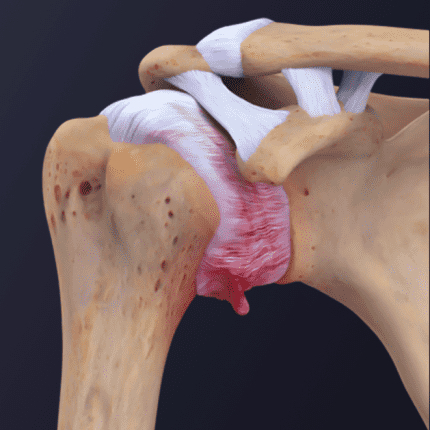

Shoulder Osteoarthritis

Goal: Preserve joint function

How: Progressive loading to improve bone density and maintain soft tissue support.